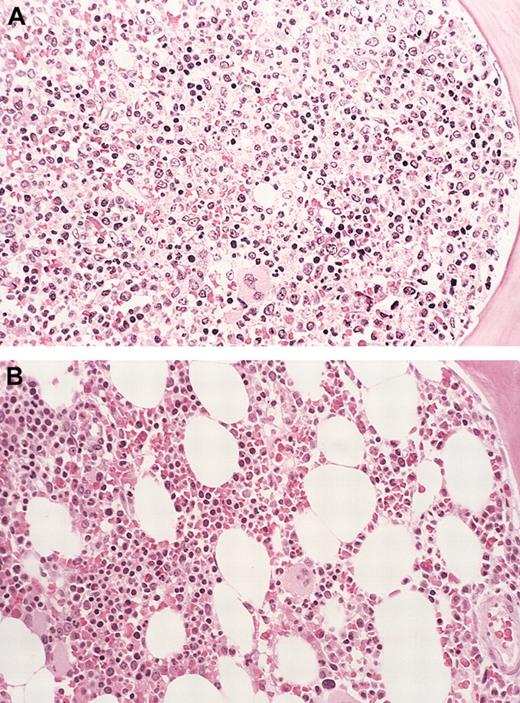

The patient had a dramatic response to therapy that was manifest both clinically, and by decreasing eosinophilia, within a week of starting treatment. At re-evaluation (12 weeks), the patient was clinically asymptomatic and reported a dramatic increase in his energy level and stamina. He had gained 9 kg in weight, and the spleen tip was no longer convincingly palpable on physical examination. Laboratory testing revealed improved hemoglobin concentration and platelet count, as well as complete resolution of the eosinophilia and leukoerythroblastic picture (Table 1). A follow-up bone marrow examination revealed a dramatic decrease in overall cellularity and resolution of eosinophilia (Figure 2). The patient at last follow-up continued to be in clinical and histologic remission.

Bone marrow eosinophil cytoreduction with imatinib therapy (case 6).

Hematoxylin-eosin (H&E)–stained bone marrow biopsy tissue (A), showing markedly hypercellular marrow with left-shifted granulopoiesis and eosinophilia before treatment with imatinib. (B) Shows the dramatic reduction in marrow cellularity with normal trilineage hematopoiesis after imatinib therapy (at 16 weeks). Original magnification for both panels, × 160.